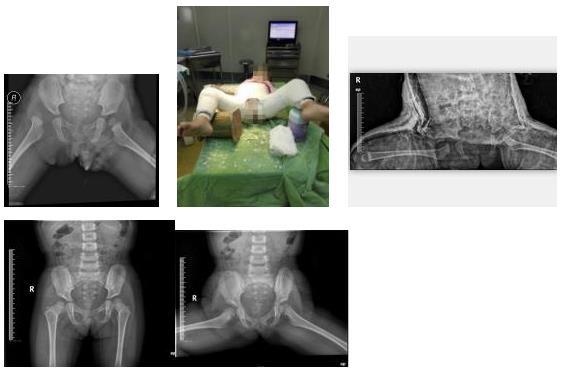

我科是区内少数能开展手术治疗发育性髋关节的科室,能运用髋人字石膏外固定,Salter、Pemberton髋骨截骨等治疗发育性髋关节脱位,技术达到区内领先水平,在国内享有较高的声誉。

右髋关节发育性脱经髋人类位石膏外固定保守治疗,保守治疗后随访5年股骨头与髋臼匹配无再脱位,股骨头发育良好,无坏死。

右髋关节发育性脱位行Pemberton髋骨截骨,股骨短缩旋转术后随访5年,股骨头与髋臼发育良好。